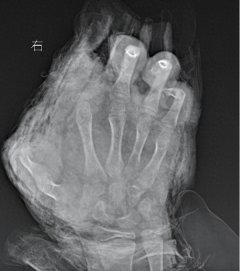

• 12岁男孩自制鞭炮,被炸断三根手指

清创 自制鞭炮 食指 2025/02/09